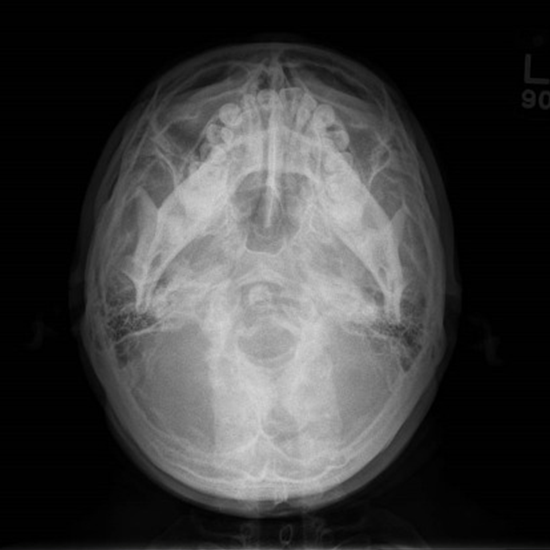

x ray base of skull

An X-ray of the skull base identifies fractures, birth malformations, infection, foreign substances, pituitary tumors, and metabolic and endocrine diseases that induce skull bone deformities. Skull X-rays can reveal brain calcifications, nasal sinuses, and cancer.